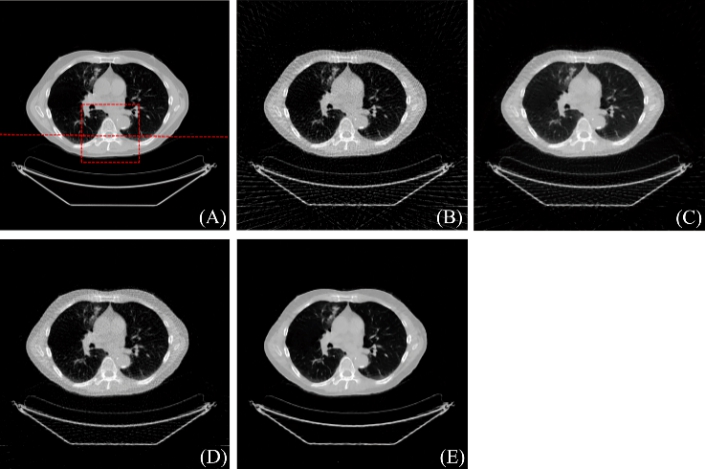

图2:重建结果. (A) 参考图像, (B) FBP重建结果, (C) PWLS-TGV重建结果, (D) R-NLTV重建结果, (E) DD-Net重建结果

图3:图2(A)中红色标记局部区域的放大图(A) 参考图像, (B) FBP重建结果, (C) PWLS-TGV重建结果, (D) R-NLTV重建结果, (E) DD-Net重建结果